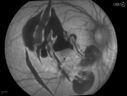

Choroidal Rupture and small Hemorrhage - Assault1307 views34 year old man. The patient reports he was assaulted by a couple of adolescents near downtown St. Petersburg about forty-eight hours ago. He reports the pain in the left eye has significantly improved, but his vision is a little fuzzy and he sees some floaters in the left eye. 20/125 OD, 20/20 OS. Pinhole improves in the right eye to 20/50. IOP: 15 OD, 13 OS.

SLIT LAMP EXAMINATION: Biomicroscopy reveals 3+ pupillary reaction OD, 2+ OS with no afferent pupillary defect. EXTENDED OPHTHALMOSCOPY: Extended funduscopy with Volk 90-diopter lens and fundus drawings of both eyes reveal a clear view with no posterior vitreous separation. C/D ratio is 0.2. There is no vitreous debris or hemorrhage. Large retinal vessels and macula are healthy. The retinal periphery, inspected with scleral depression for 360° shows no retinal tears, breaks, or detachments.